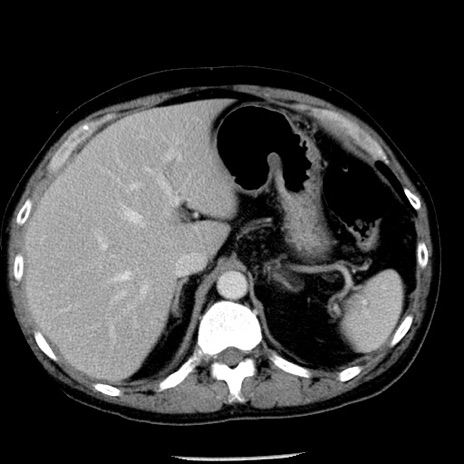

冠状断像

【症例】40歳代男性

【現病歴】2日前から胃痛あり。徐々に周期的な激痛に変化した。本日になっても激痛があるため受診。

【身体所見】意識清明、BT 38-39℃台あり、腹部:膨満、やや硬、右下腹部に圧痛あり。

【データ】WBC 8500、CRP 23.26